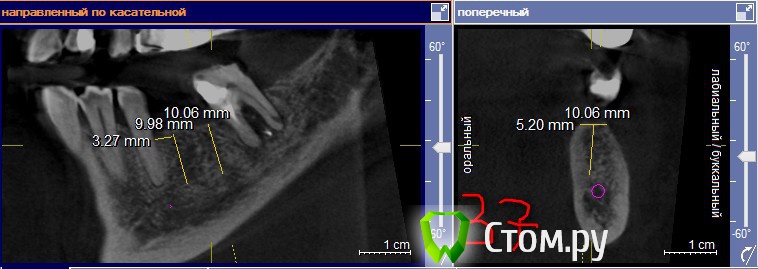

lavrikk Опубликовано 10 мая, 2014 Поделиться Опубликовано 10 мая, 2014 Коллеги, планируется установка имплантантов на Н.Ч. в области 36,37, 46, 4738 удален 10 дней назад, 48 решено сохранять, устраняя наклон ортопедической конструкцией.Смущает толщина гребня-планирую ставить 3.4-10(8) мм Dentium, но платформа у него 3.6.Понимаю необходимость НКР и справа и слева, но ниразу не делал(Вопрос вот в чем, лучше установить импланты в правильные позиции и что будет не в кости засыпать ауто+ксено и мембрана,либо сошлифовать гребень установить более апикально для выигрывания ширины.А также вопрос-как поступаете когда остался небольшой остаток корня в области проекции винта в кости(как на 47), удаляете заранее или во время имплантации аккуратно?Буду благодарен за любую помощь! Ссылка на комментарий

lavrikk Опубликовано 10 мая, 2014 Автор Поделиться Опубликовано 10 мая, 2014 По моему хорошие условия по высоте и ширине кости, узкий гребень думаю можно чуть сравнять с "землей")А как быть с корешком на глубине 3-4 мм? Ссылка на комментарий

diesel87 Опубликовано 10 мая, 2014 Поделиться Опубликовано 10 мая, 2014 А как быть с корешком на глубине 3-4 мм?А это точно остаток корня? Ссылка на комментарий

lavrikk Опубликовано 11 мая, 2014 Автор Поделиться Опубликовано 11 мая, 2014 А это точно остаток корня?Почему то не раздумывая так написал. А что еще может быть? По денситометрии цифры плотности на к/т как у зубов. Ссылка на комментарий

faity Опубликовано 11 мая, 2014 Поделиться Опубликовано 11 мая, 2014 Почему то не раздумывая так написал. А что еще может быть? По денситометрии цифры плотности на к/т как у зубов.цементома, гиперцементоз. Ссылка на комментарий

lavrikk Опубликовано 11 мая, 2014 Автор Поделиться Опубликовано 11 мая, 2014 цементома, гиперцементоз.аВ если это цементома? Какова тактика? Во время формирования ложа под имлантат упрусь во что то твёрдое? Если зуб то линдеман не пройдет через него, если цементома - то пройдет. В чем тут опасность может быть? Ссылка на комментарий